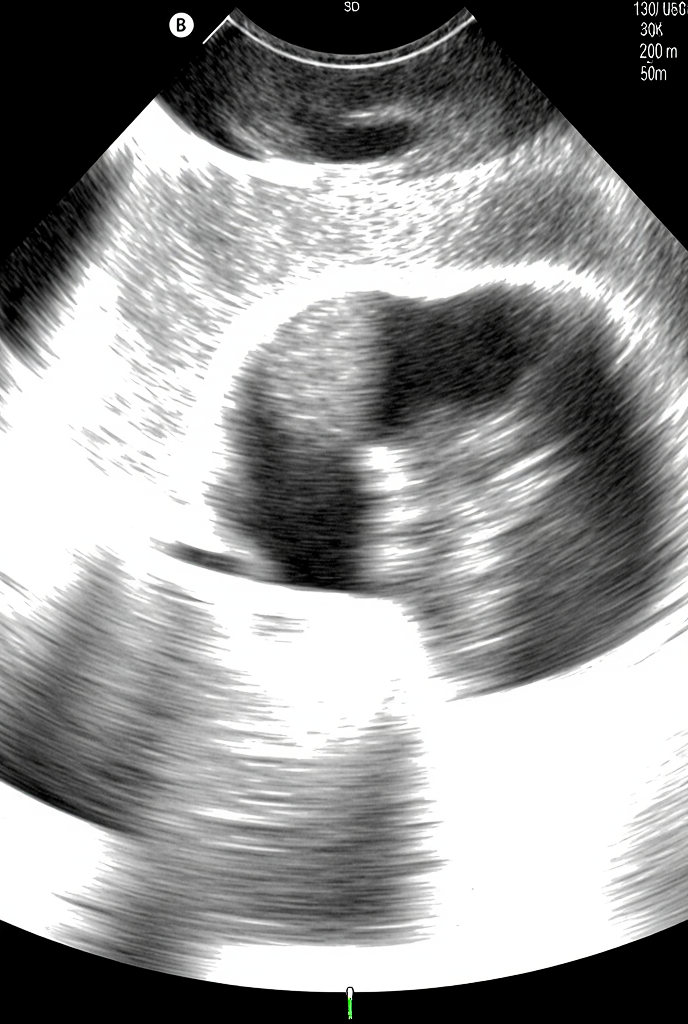

Rahim Filmi, tıp literatüründe Histerosalpingografi (HSG) olarak bilinen bir görüntüleme yöntemidir. Bu işlem, kadın üreme sağlığını değerlendirmek amacıyla, rahim boşluğunun ve fallop tüplerinin yapısını, şeklini ve açıklığını kontrol etmek için kullanılır.

Histerosalpingografi (HSG) olarak da bilinen rahim filmi, infertilite (kısırlık) değerlendirmesinde kritik bir rol oynayan görüntüleme yöntemidir. Bu işlemde, rahim ve fallop tüplerinin yapısını, şeklini ve açıklığını değerlendirmek için X-ışını altında görünen özel bir kontrast madde (boya) kullanılır. Özellikle tüp tıkanıklığı şüphesi olan durumlarda başvurulan HSG, spermin yumurtaya ulaşmasını veya döllenmiş yumurtanın rahme inmesini engelleyebilecek sorunları tespit etmeyi hedefler. İşlem, genellikle adet döngüsünün 8. ile 12. günleri arasında yapılır, bu sayede hem doğru sonuç elde edilir hem de olası bir gebelik riski önlenir.